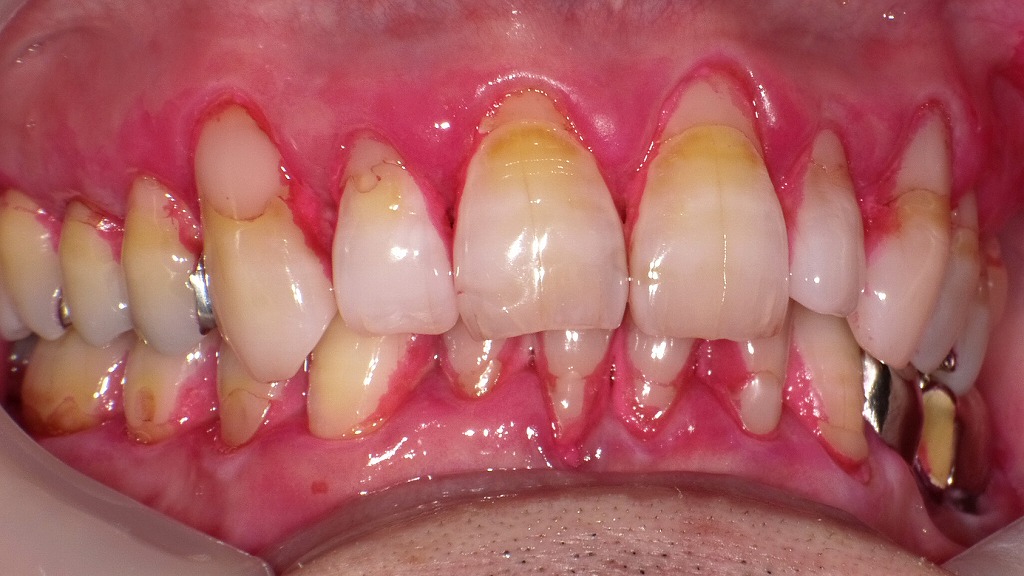

この部位の清掃改善は、治療効果に直結します。歯磨き指導と歯石除去後で歯ぐきの炎症が大きく改善

① 正面写真:歯肉の炎症が大きく改善した状態

歯磨き指導と歯石除去により、歯肉の赤み・腫れが大幅に改善。

プラークと縁上歯石が除去されたことで、歯肉が引き締まり、出血の消失も確認できます。治療前に比べて、明らかに次の改善が確認できます。

【改善ポイント】

- 歯肉の赤み(発赤)が大幅に軽減

- 腫れが引き、歯肉の輪郭が明瞭に

- 自然出血が消失し、引き締まった歯肉に近づいている

- 前歯部の縁上歯石と着色の減少が明らか

歯肉が落ち着いており、プラークコントロールが改善したことに加え、スケーリングによる刺激源除去が効果的であったと考えられます。

② 右側写真:歯肉縁の炎症の沈静化とプラーク減少

治療前に強く出ていた歯肉炎症が、清掃指導とスケーリング後に明らかに軽減。

健康なピンク色に近づき、歯肉の輪郭もはっきりと見えるようになりました。治療前は腫れと強い発赤、縁下歯石が疑われる状態でしたが、治療後は以下の改善が見られます。

- 歯肉の色調が健康なピンクに近づいた

- 歯肉の腫脹が軽減し、ポケット辺縁の形が明確に

- 歯の根元のプラークが減少

- ブラッシング指導が反映され、歯間部の汚れが大幅に減少

右側は特に炎症が強かった部位ですが、ホームケアの改善がよく反映された写真です。

③ 左側写真:プラークコントロールの習得が反映された清潔な状態

磨き方の見直しと歯石取りで、歯ぐきの赤みや腫れが落ち着きました。

歯ブラシがきちんと当てられるようになり、お口全体が清潔な状態になっています。左側も治療前と比較し、次のような大きな変化が確認できます。

- 縁上歯石の除去により、歯肉縁の赤みが減少

- 歯間部・歯頸部のプラークが明らかに少ない

- 炎症による光沢(浮腫状のテカリ)が減少し、健康歯肉に

- 全体的にブラッシングが均等に行われている印象

歯肉の腫れが引いたことで、治療前には見えにくかった歯の形態も明瞭になっています。